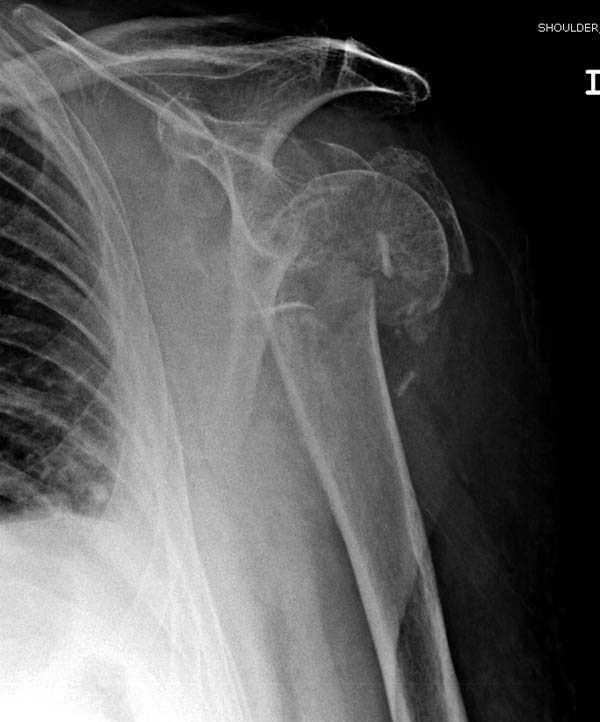

Re: Шейка плеча

дополнительные снимки по протезированию